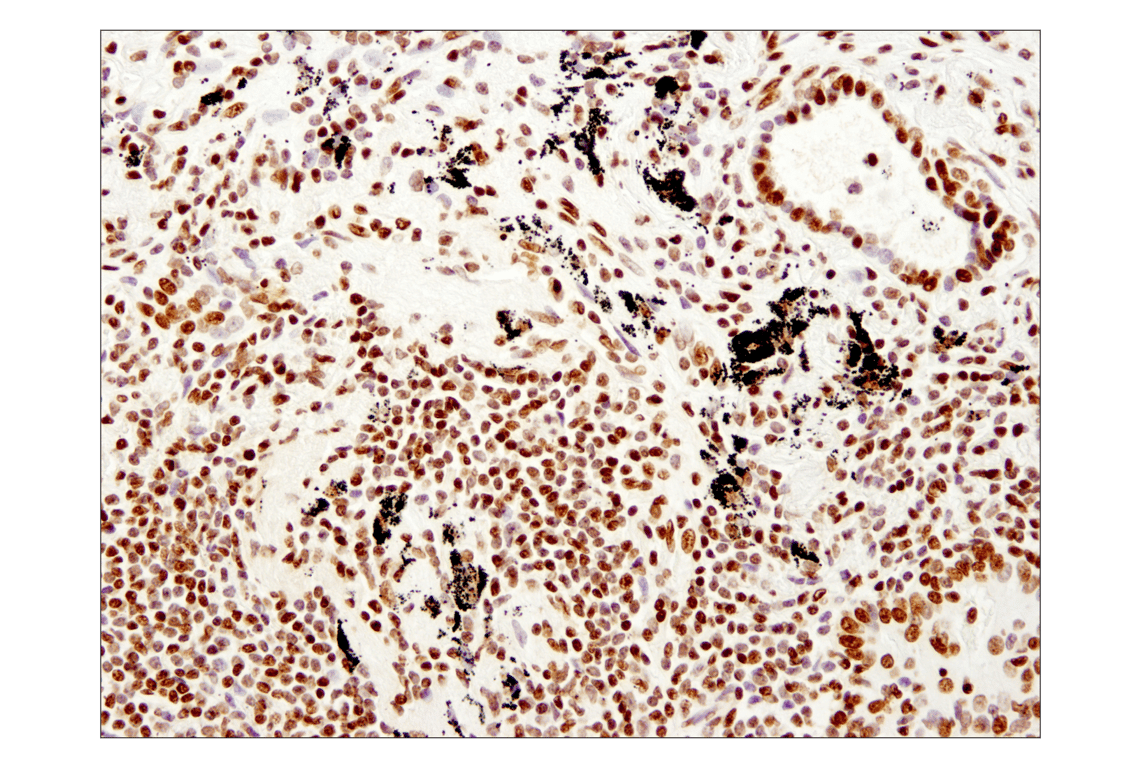

| Immunohistochemistry (Paraffin) | 1:250 - 1:1000 |